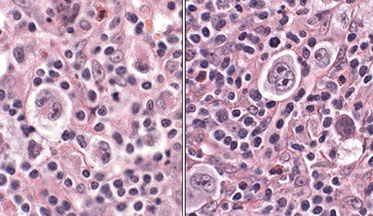

Classic Hodgkin Lymphoma (cHL)

- Mixed-cellularity classic Hodgkin lymphoma